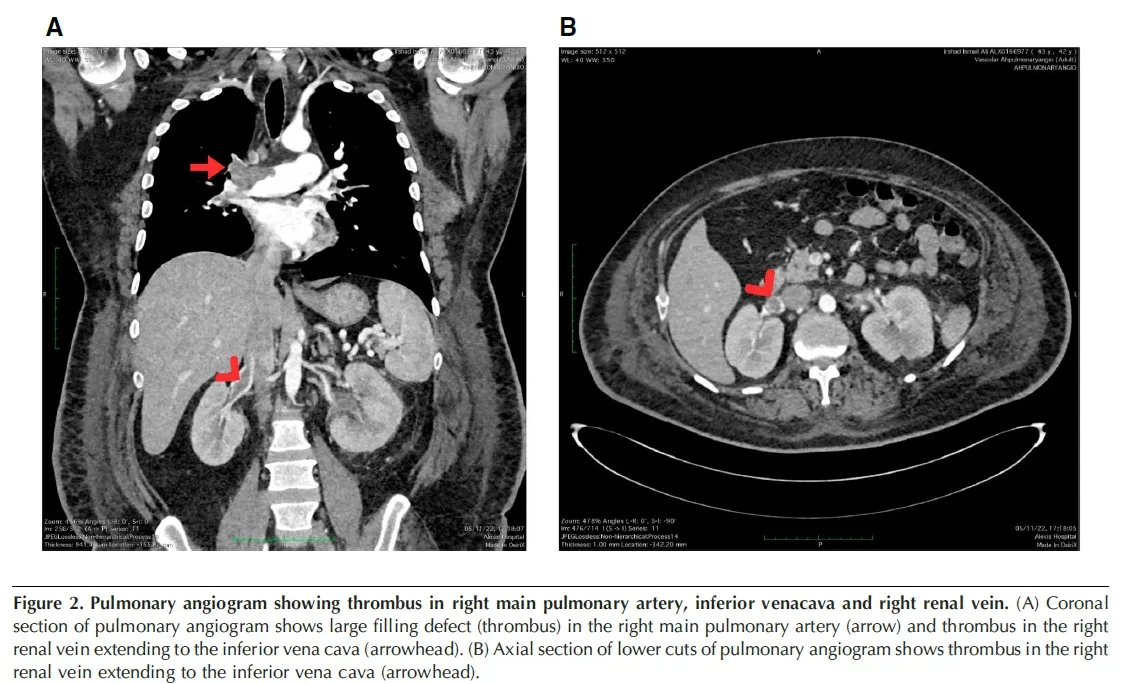

Um dia após a biópsia, o paciente apresentou dispneia súbita, taquicardia e hipotensão. Ecocardiograma revelou dilatação do tronco da artéria pulmonar e do ventrículo direito. A tomografia computadorizada de tórax confirmou tromboembolismo pulmonar associado a trombose da veia cava inferior e veia renal direita. Foi realizada trombólise com alteplase, sem intercorrências hemorrágicas, seguida de anticoagulação com rivaroxabana.